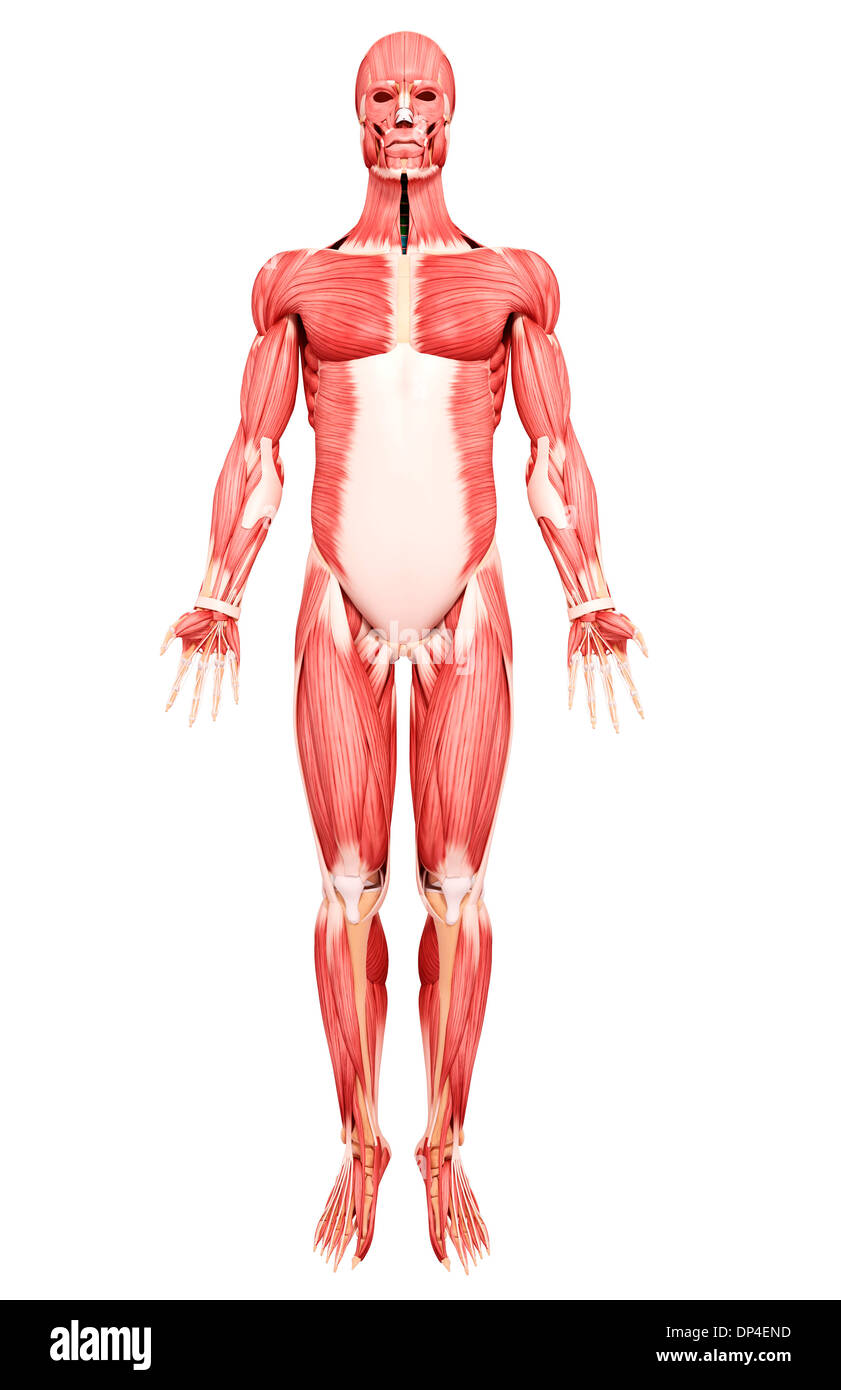

Les droits de l'Anatomy, artwork Banque D'Imageshttps://www.alamyimages.fr/image-license-details/?v=1https://www.alamyimages.fr/les-droits-de-l-anatomy-artwork-image65252921.html

Les droits de l'Anatomy, artwork Banque D'Imageshttps://www.alamyimages.fr/image-license-details/?v=1https://www.alamyimages.fr/les-droits-de-l-anatomy-artwork-image65252921.htmlRFDP4END–Les droits de l'Anatomy, artwork